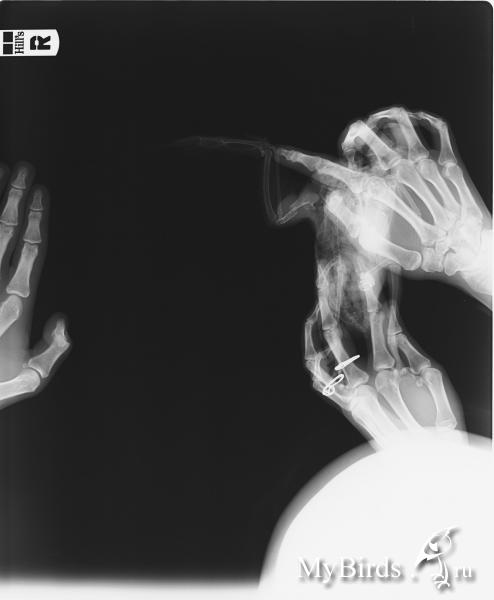

Сегодня подобрала малыша - сломана плечевая кость. Снимок рентгеновский прилагаю. Орнитолог в лучшем случаем пример во вторник, в худшем - в пятницу. Нужно как-то зафиксировать крыло! Подскажите, пожалуйста, как это лучше сделать, чтобы не навредить!

post-45623-1465661804_thumb.jpg